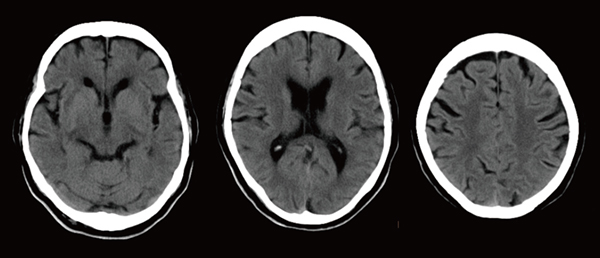

[CT 5300の臨床画像]

ノイズを低減した高画質頭部単純画像

(Precise Image,5mmスライス画像)

「Precise Imageによって以前よりもノイズが大幅に低減し,コントラストが向上しているため,3D画像の作成においては,ワークステーションによる骨や血管の自動抽出の精度が向上しました。末梢血管は通常,ノイズに埋もれてコントラストも付きにくく,3D画像の作成が非常に難しいのですが,現在は作成の手間が以前の半分以下になり,ストレスも軽減しています。また,頸部の撮影では肩のアーチファクトが劇的に低減し,鎖骨下動脈や肩周りの画像再構成が簡単に行えるようになりました」

Precise Imageは,さまざまなシチュエーションでも高画質が得られることから,今後は頭部領域の線量低減にも期待が寄せられている。また,低線量肺がん検診CTの画質改善も期待できる。患者の負担を軽減しつつ,診断に役立つ画像を迅速に提供し続けていくことで,CT 5300は,同院がめざす理想の医療を支え続けていくに違いない。